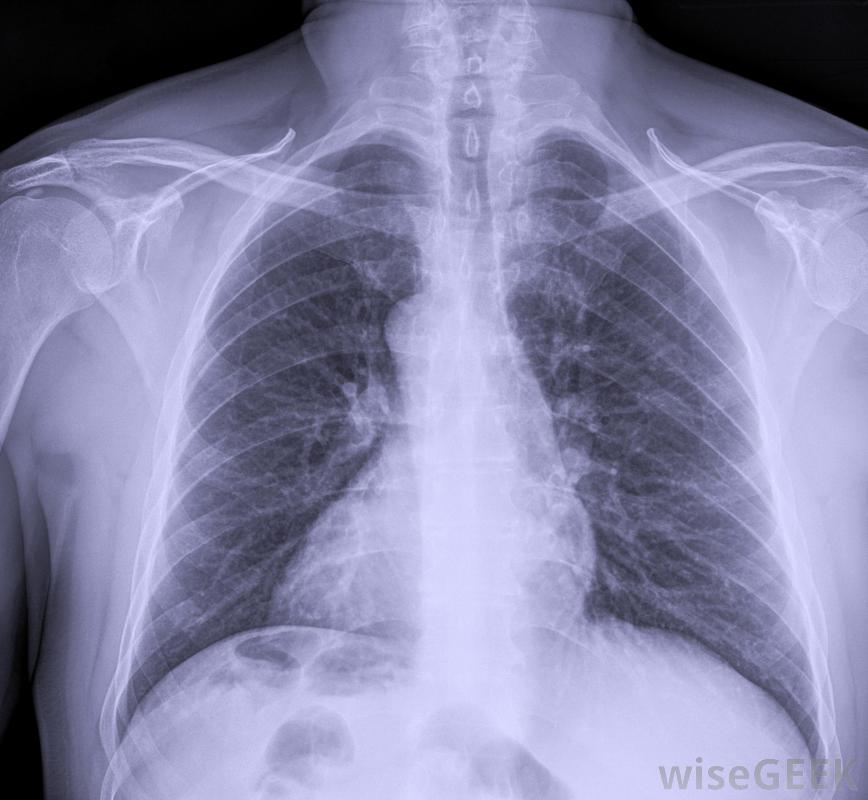

胸膜纖維化是胸膜(覆蓋肺部的組織)發展成纖維組織的一種情況。在正常情況下,胸膜是一種非常柔軟的粘液膜,但當胸膜纖維化發生時,胸膜變厚變硬。纖維生長是良性的,但如果廣泛存在,可能會給患者帶來并發癥,并且可能與對患者有害的疾病過程有關。胸膜纖維化影響覆蓋肺部的組織胸膜纖維化有多種原因,通常與石棉暴露有關,病理學家在嚴重情況下對胸膜進行解剖時,常常發現胸膜中嵌入石棉纖維,有時長達15年,也可能是由炎癥過程、手術創傷或胸腔積液引起的。在輕度病例中,這種情況會導致小面積的纖維組織發育,這可能不會給患者帶來任何問題,并且在胸部x光片上也會發現與此無關的原因將檢查胸部X光片是否有胸膜纖維化的跡象當胸膜嚴重時,整個肺組織會變得很致密,像是很容易膨脹的白色組織當胸膜增厚時,肺不得不更加努力地充氣,最終增厚的組織會損害肺功能,使病人無法呼吸或呼吸極度困難。在這種情況下,受損的胸膜必須手術切除,這樣肺部才能充氣即使是輕度病例,也經常建議進行活檢,以確認生長是良性的,而不是癌癥。病情嚴重的病人會因為呼吸困難而尋求治療。醫生可以通過胸部x光片等工具來診斷病情,對可疑組織進行活檢,并聽肺部的聲音。即使是輕微的病例,也經常建議進行活檢,以確認腫瘤是良性的,而不是癌性的,因為癌癥的治療方法與胸膜纖維化的治療方法大不相同隨著胸膜增厚,肺不得不更加努力地充氣,導致呼吸困難。胸膜中也可能出現胸膜鈣化和胸膜纖維化鈣化,胸膜上出現小的白色斑塊。在輕度病例中,這些斑塊可能沒有問題,但如果它們變大、擴散,或與廣泛的胸膜纖維化相關,則可引起關注纖維化也可能發生在臟器周圍的粘液膜上,例如心臟和腸道。病理學家經常在胸膜中發現石棉纖維,以防接觸導致胸膜纖維化。